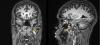

• María José Hernández García | 30-Mar-2021

Paciente mujer de 47 años que consulta por dolor ocular sin disminución de agudeza visual ni otra sintomatología acompañante salvo tinnitus fluctuante. La paciente no tiene antecedentes personales de interés, peso normal. En exploración oftalmológica...

Caso completo | PDF

Neurología: NeurooftalmologiaEtiología: Malformación vascularDiagnóstico final: fístula arteriovenosa duralNivel de certeza: